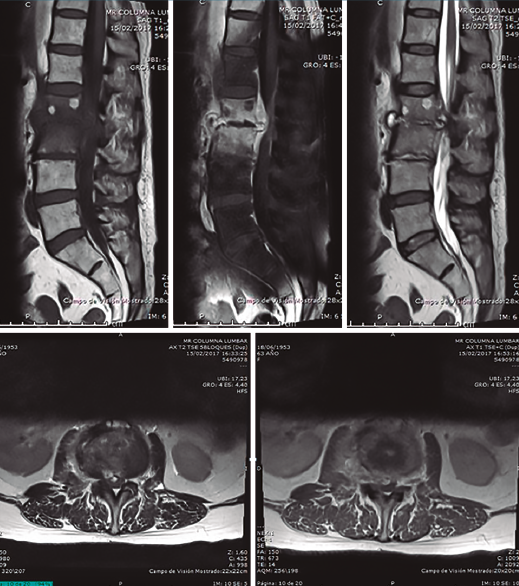

Figura 4. Resonancia magnética al ingreso en nuestra unidad. Secuencias T1 y T2 sagitales y axiales. Destrucción discal, edema masivo en disco y vértebras adyacentes, y colecciones líquidas anteriores y posteriores, disecando incluso psoas iliaco.

Se realizó analítica completa: hemograma normal, marcadores proteína C reactiva (PCR) y velocidad de sedimentación globular (VSG) claramente elevados, 80 y 63 respectivamente, Rx y RM (Figuras 1 a 4).

Con la orientación diagnóstica de espondilodiscitis aguda, se realizó punción biopsia guiada por tomografía computarizada (TC). Identificamos el germen Streptococcus bovis: coco Gram positivo, comensal del aparato digestivo humano y de otros mamíferos, y que está principalmente implicado en bacteriemias/sepsis, endocarditis e infecciones urinarias y del sistema nervioso central. La asociación entre infección sistémica por S. bovis y cáncer de colon es relativamente frecuente.